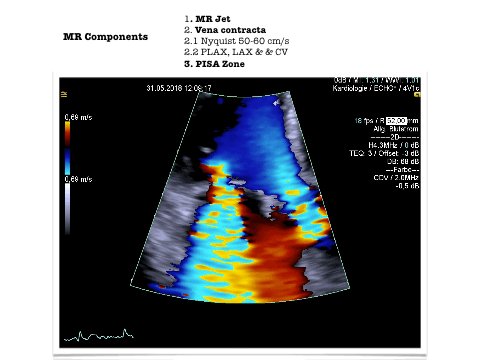

#echofirst 1/9 When looking & reporting MR there is so many parameters to consider. We need to understand mechanism and secondary changes. Trying to put some points together

2/9 this is short representation on PISA from Braunwald

3/9